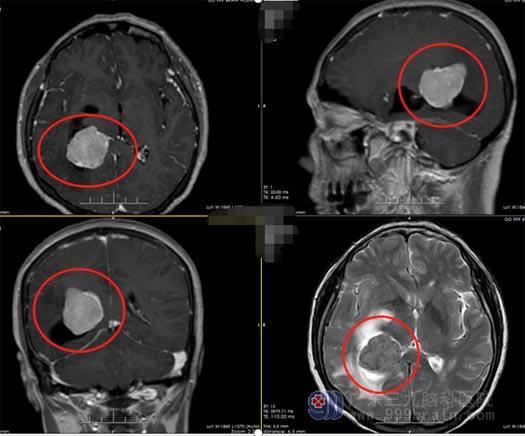

来自江西的楼大姐,今年57岁。大约两周前,没有诱因的情况下出现了头晕,一直持续无好转,便去往当地医院就诊,头颅MR显示右侧侧脑室占位性病变,考虑为脑膜瘤,医生建议进行手术治疗。

▲术前